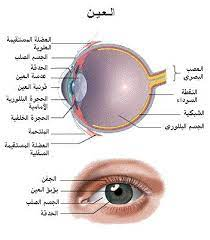

البصر والعين

أجزاء العين

يدخل الضوء الى العين من خلال القرنية وهي طبقة شفافة تحيط بالمنطقة الملونة في العين القزحية وظيفة القرنية تركيز الضوء وادخاله الى العين

في مقدمة العين توجد فتحة مستديرة تسمى البؤبؤ ويحيط بالبؤبؤ قرص مستديرة ملون هو القزحية

تتحكم القزحية في مقدار الضوء الذي يدخل العين وذلك عن طريق تغيير حجم البؤبؤ فعندما يكون الضوء خافتاً، يتسع البؤبؤ ليسمح لكمية أكبر من الضوء بالدخول.

خلف البؤبؤ توجد قطعة من نسيج شفاف تسمى العدسة، نسبة إلى عدسة الكاميرا، تساعد على انكسار الضوء على الشبكية.

في الخلف تقوم طبقة من نسيج عصبي يدعى الشبكية. وهي تحتوي على خلايا عصبية هي مستقبلات الضوء. وتتصل الشبكية في الخلف بالـ عصب البصري الذي يتصل بالدماغ